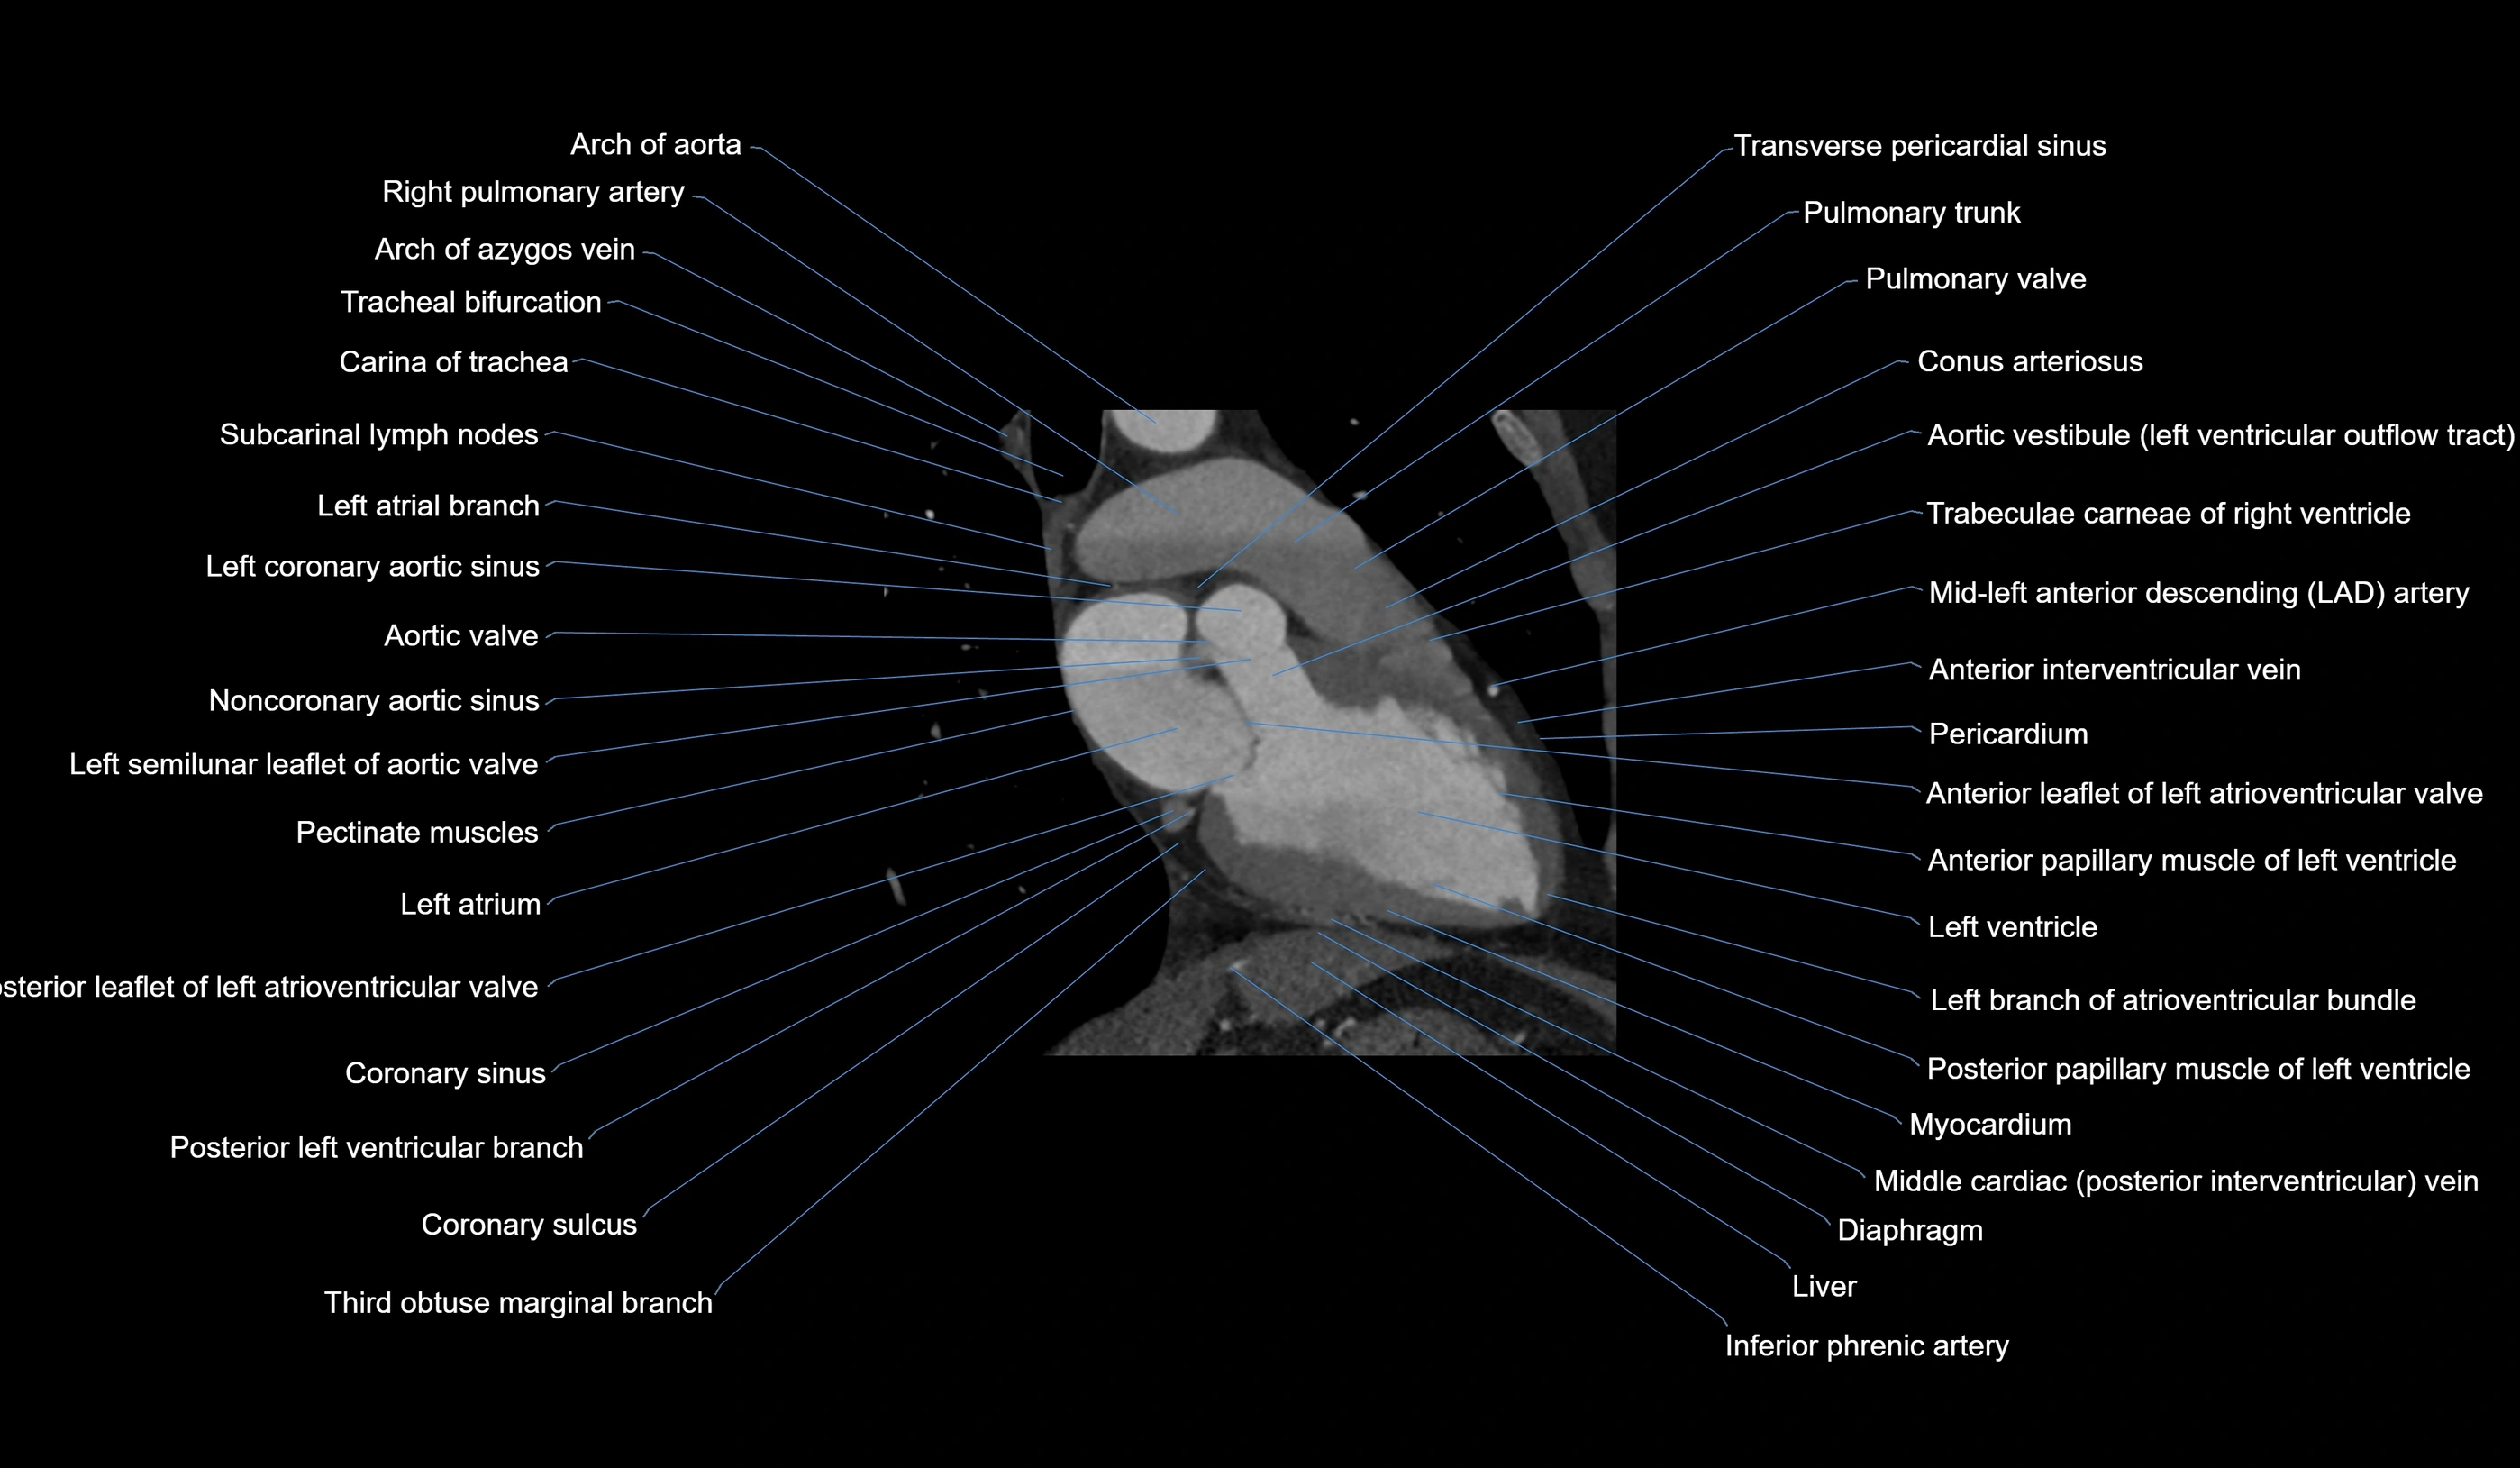

CT Appearance

CT Coronary Angiography (CCTA):

-

Best non-invasive modality for acute marginal artery visualization

Shows origin, course along the acute margin, and right ventricular branches

Detects stenosis, occlusion, calcified and non-calcified plaques, aneurysm, or anomalous course

Multiplanar reformats and 3D reconstructions help in pre-PCI and surgical planning

Critical for assessing right ventricular infarction risk in RCA disease

MRI image

CT images